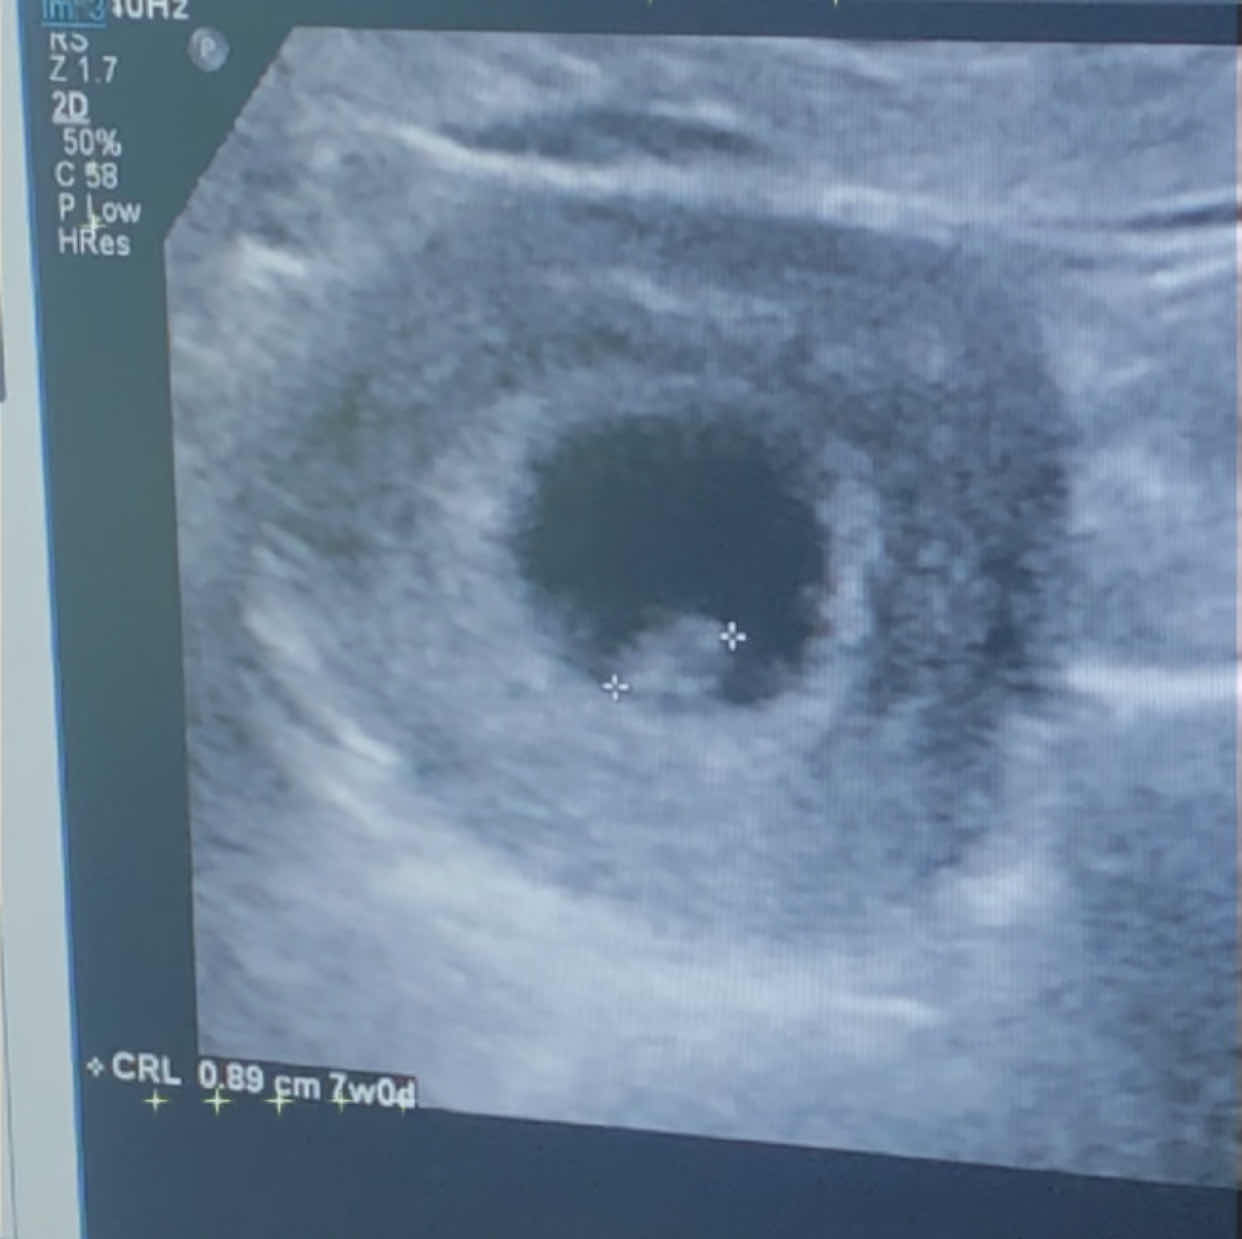

انا دورتي 4 مايو عملت سونار لما وصلت الاسبوع 7وقالولي عمر الجنين6 اسابيع واليوم رجعت عملت سونار لما وصلت 9...